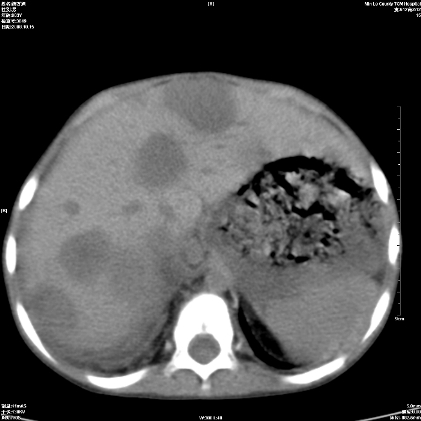

标题: PED1609:男性,3岁。彩超示肝Ca. [打印本页]

标题: PED1609:男性,3岁。彩超示肝Ca.

3岁;肝低密度灶;有钙化;有转移灶;考虑肝母细胞瘤;查afp

支持肝母细胞瘤肝内转移

考虑神经母细胞瘤并肝转移

考虑:1、右侧后下纵隔畸胎瘤。

2、肝脏多发血管内皮细胞瘤。

建议:增强确诊。